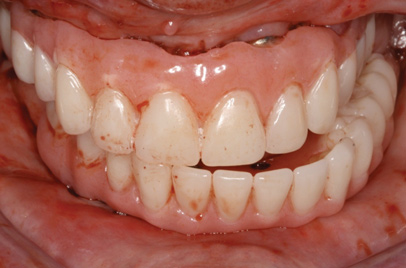

Fig 7. Existing dentition was sound periodontally and reasonably esthetic.

Figure 7